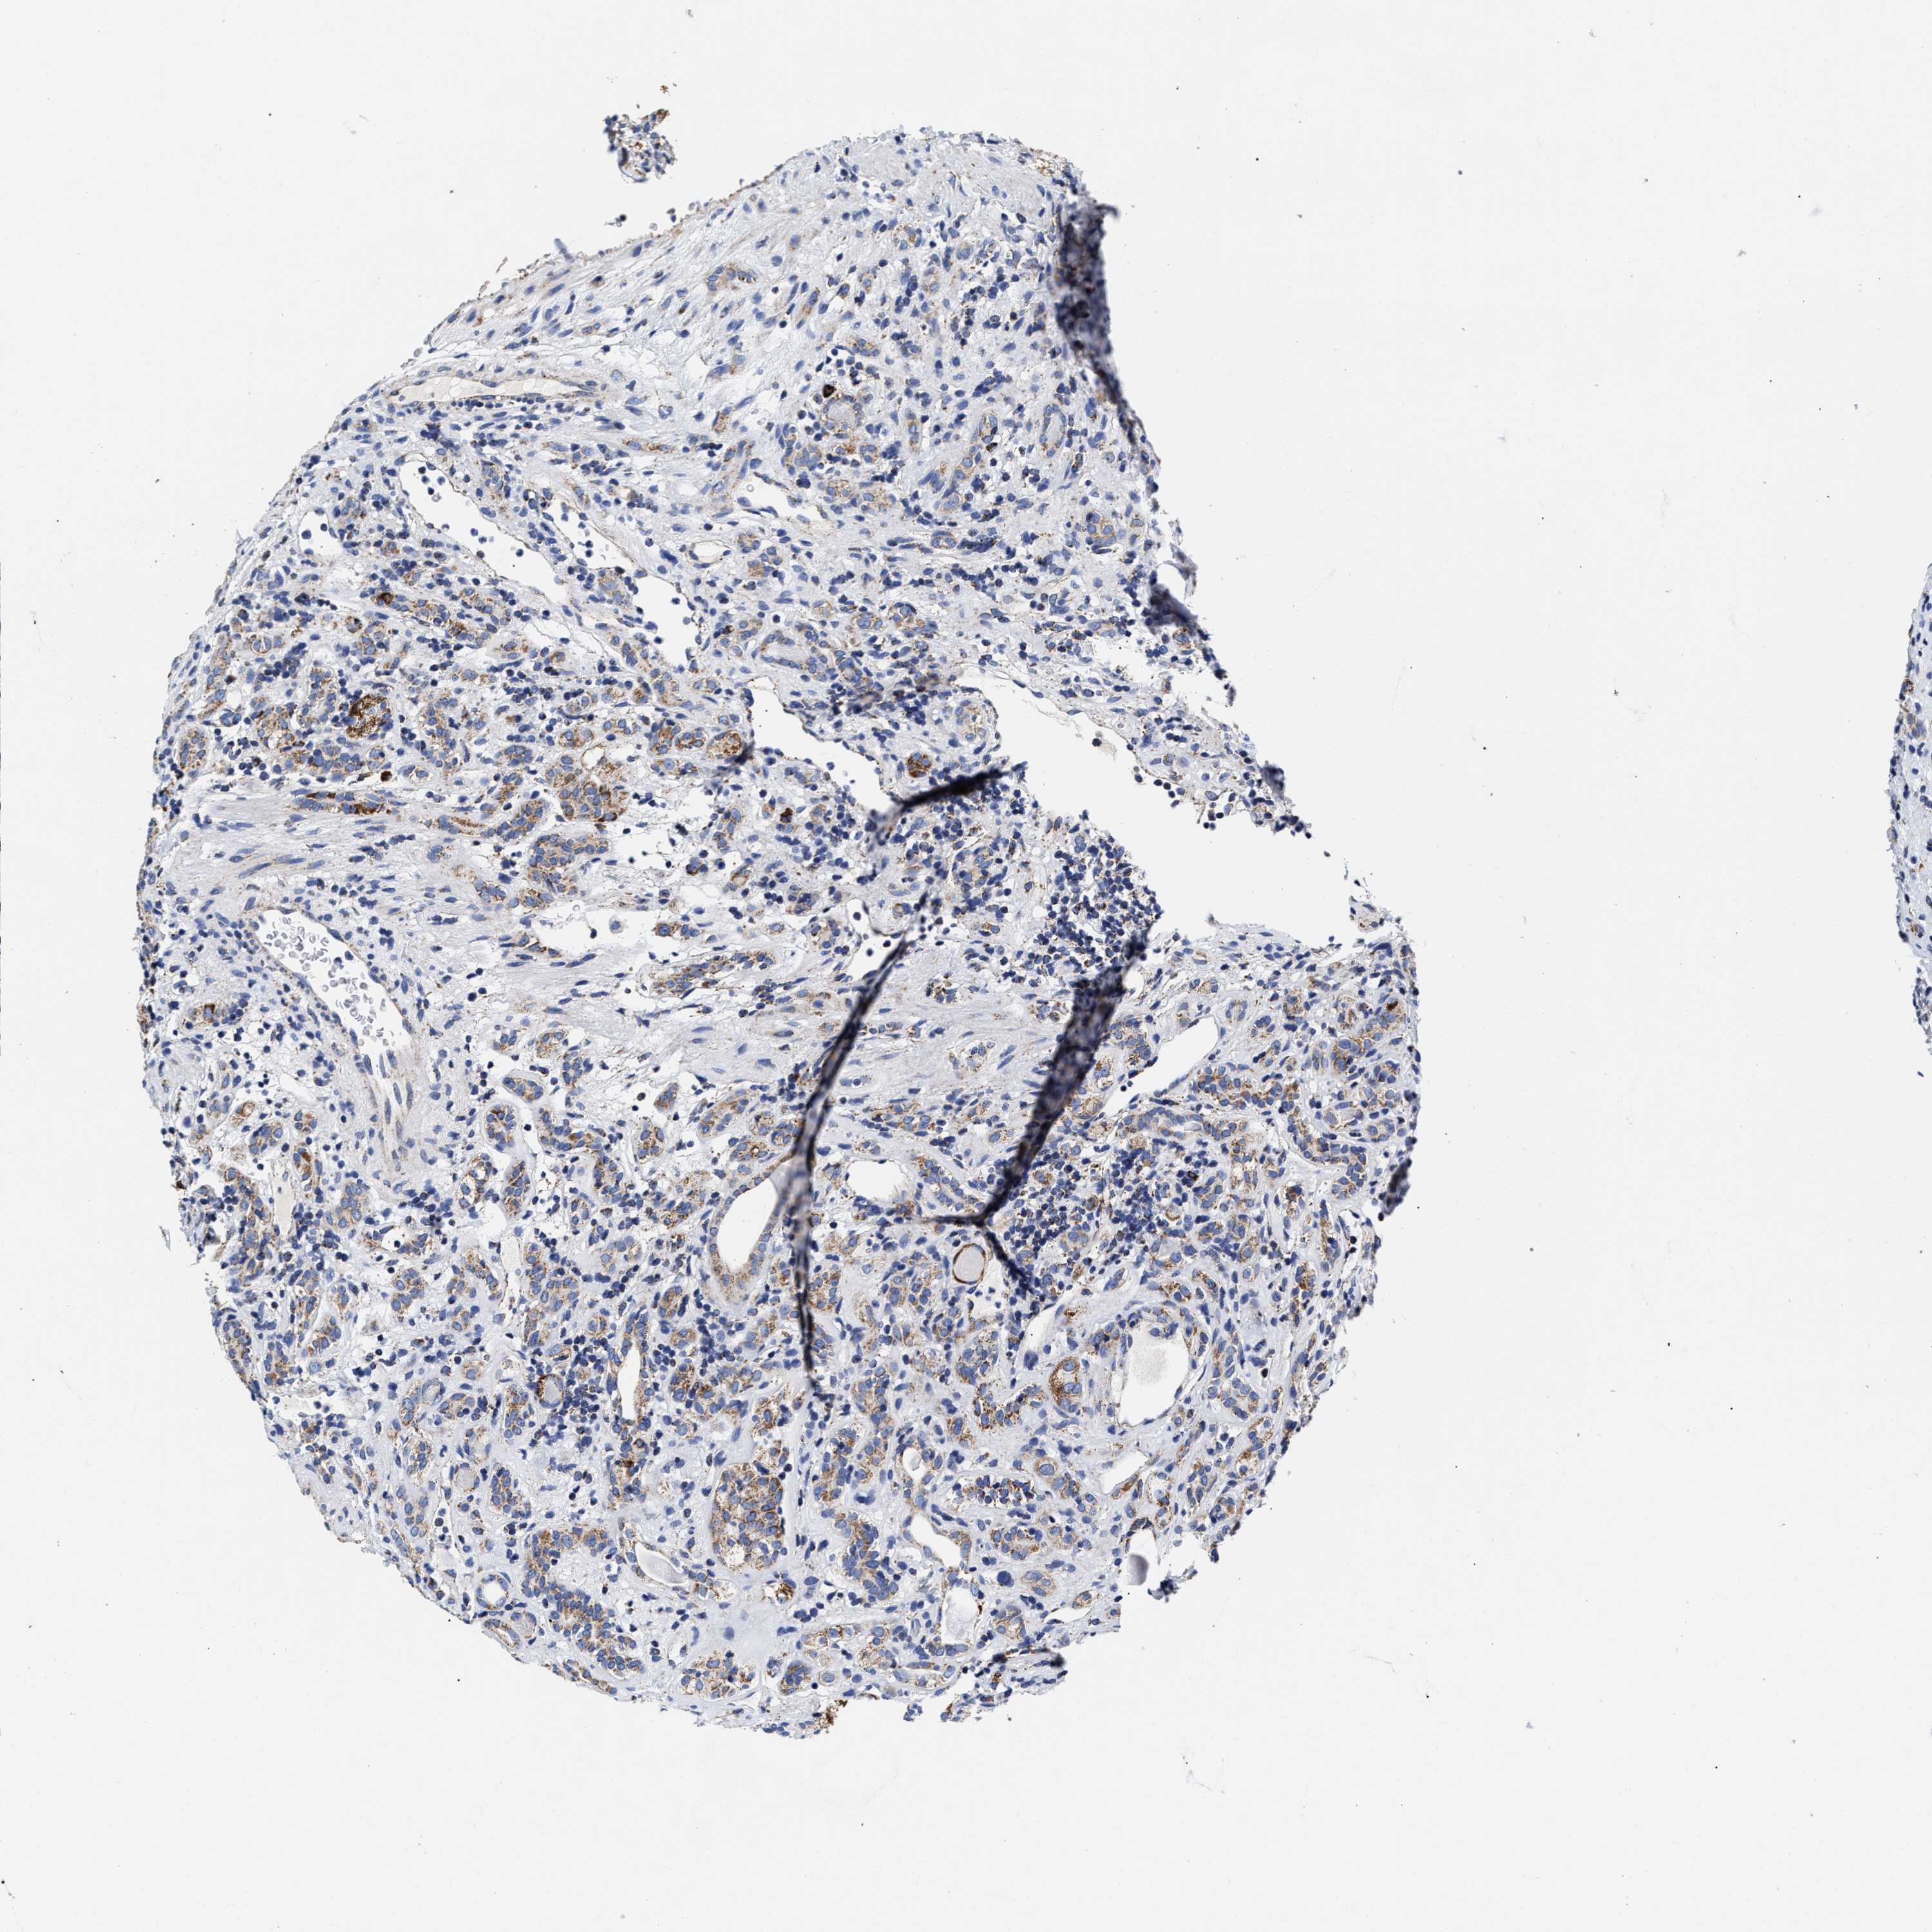

KIDNEY RENAL CLEAR CELL CARCINOMA (VALIDATION) - Interactive survival scatter ploti

The Survival Scatter plot shows the clinical status (i.e. dead or alive) for all individuals in the patient cohort, based on the same data that underlies the corresponding Kaplan-Meier plots. Patients that are alive at last time for follow-up are shown in blue and patients who have died during the study are shown in red.

The x-axis shows the expression levels (FPKM) of the investigated gene in the tumor tissue at the time of diagnosis. The y-axis shows the follow-up time after diagnosis (years). Both axes are complimented with kernel density curves demonstrating the data density over the axes. The top density plot shows the expression levels (FPKM) distribution among dead (red) and alive patients (blue). The right density plot shows the data density of the survived years of dead patients with high and low expression levels respectively, stratified using the cutoff indicated by the vertical dashed line through the Survival Scatter plot. This cutoff is automatically defined based on the FPKM cutoff that minimizes the p-score. The cutoff can be changed by dragging the vertical line or by entering a cutoff value in the square labeled "Current cut-off".

Under the Survival Scatter plot the p-score landscape (black curve; left axis) is shown together with dead median separation (red curve; right axis). Dead median separation is the difference in median mRNA expression between patients who have died with high and low expression, respectively. It is calculated as follows: median FPKM expression of dead patients with high expression - median FPKM expression of dead patients with low expression. This is intended to aid the user in visually exploring custom cutoffs and the associated p-scores and dead median separation.

Individual patient data is displayed and can be filtered by clicking on one or more of the category buttons on the top of the page. Categories describing expression level and patient information include: high, low, alive, dead, female, male and tumor stages. The scale of the x-axis can be toggled between linear and log-scale by clicking on the "x log" button. Mouse-over function shows TCGA ID, patient information and mRNA expression (FPKM) for each patient.

& Survival analysisi

Kaplan-Meier plots summarize results from analysis of correlation between mRNA expression level and patient survival. Patients were divided based on level of expression into one of the two groups "low" (under cut off) or "high" (over cut off). X-axis shows time for survival (years) and y-axis shows the probability of survival, where 1.0 corresponds to 100 percent.

HINT2 is not prognostic in Kidney Renal Clear Cell Carcinoma (validation)

Best expression cut offi

Based on the FPKM value of each gene, patients were classified into two groups and association between prognosis (survival) and gene expression (FPKM) was examined. The best expression cut-off refers the FPKM value that yields maximal difference with regard to survival between the two groups at the lowest log-rank P-value. Best expression cut-off was selected based on survival analysis .

When clicking on this number, the vertical dashed line indicating cut-off, the interactive survival plot, and the Kaplan-Meier curve will be adjusted to show results based on the best expression cut-off.

: 46.41

TCGA RNA samplesi

RNA-seq data is reported as average FPKM (number Fragments Per Kilobase of exon per Million reads), generated by the The Cancer Genome Atlas (TCGA) .

Normal distribution across the dataset is visualized with box plots, shown as median and 25th and 75th percentiles. Points are displayed as outliers if they are above or below 1.5 times the interquartile range. FPKM values of the individual samples are presented next to the box plot.

Average pTPM 55.8

Number of samples 100